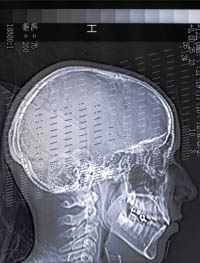

xray of human skull

Photosampler, Shutterstock (see reuse policy).